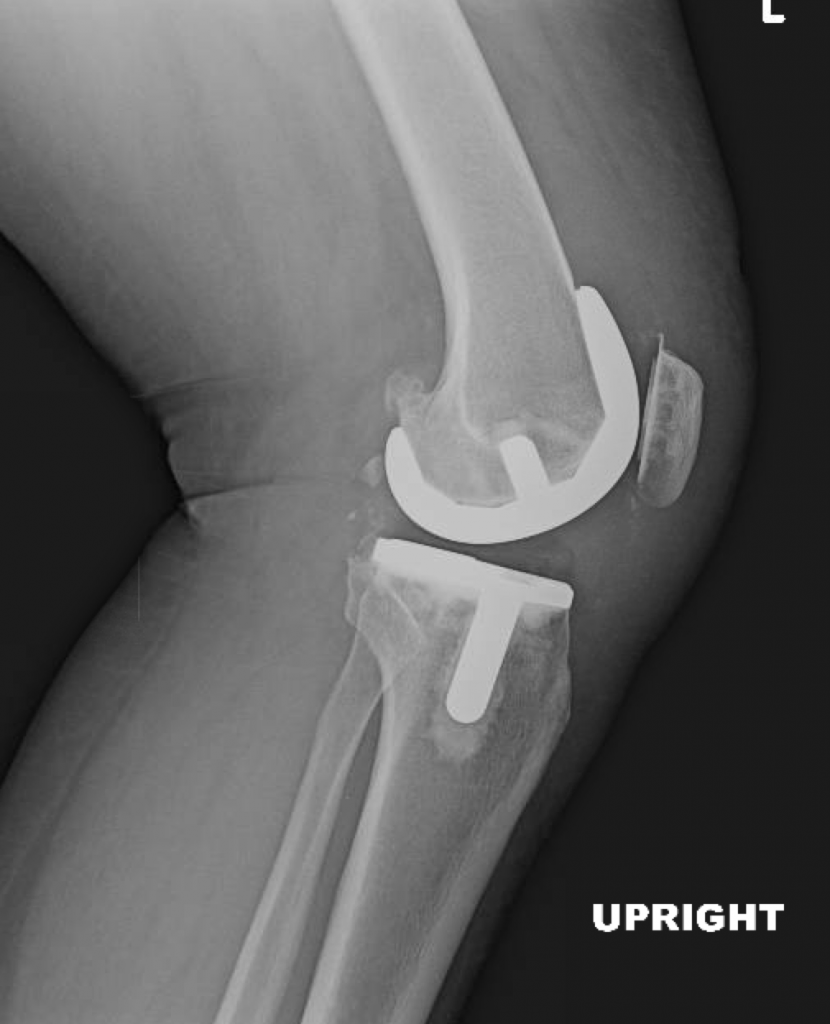

The patient’s customized surgical plan and individualized implants were created specifically for her based off of a CT scan of her knee.

At her 2 week postoperative visit, she was walking with a cane only for long distances and had a range of motion of 0-115.